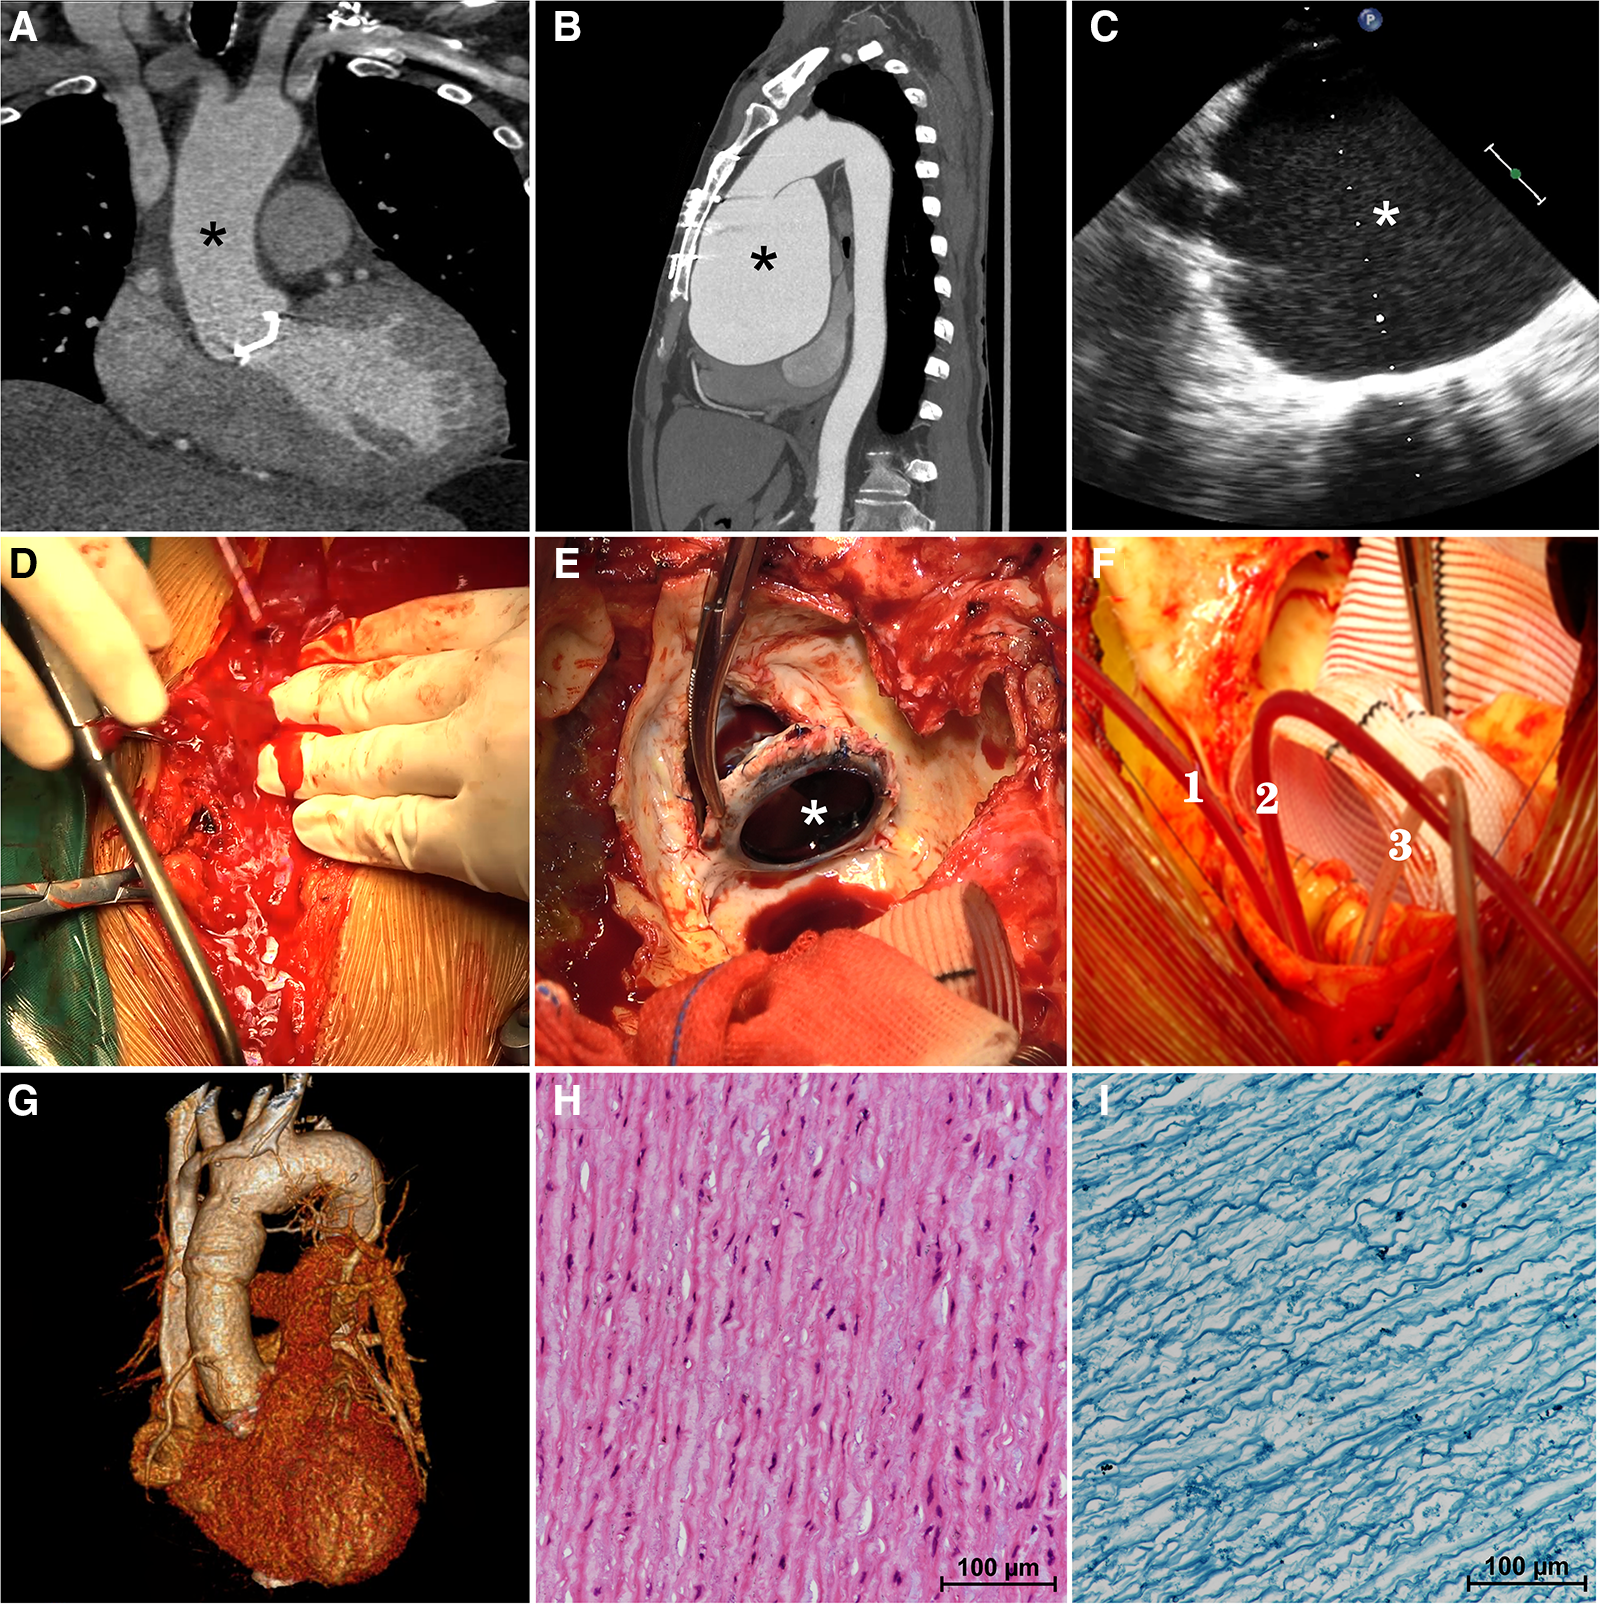

The patient in question is a 57-year-old male who underwent mechanical aortic valve replacement and ascending aortoplasty surgery at our center three years ago due to severe aortic valve regurgitation and ascending aorta dilation (4.2 cm) caused by BAV. At the time of his discharge, a Computerized Tomography Angiography (CTA) was performed, which revealed a normal aortic diameter of 3.0 cm (Figure 1A, asterisk). However, the patient did not return for follow-up examinations at our center after being discharged.

On computerized tomography angiography (CTA) performed at the time of his discharge three years ago, the aortic diameter was measured to be a normal 3.0 cm (A, asterisk). The preoperative computerized tomography angiography (B) confirmed a giant aortic root aneurysm (asterisk) bulging against the sternum. The transesophageal echocardiography (C) confirmed a giant aortic root aneurysm (asterisk) and a functional aortic mechanical valve during the operation. The aortic aneurysm ruptured suddenly during re-sternotomy (D) previous mechanical aortic valve (E, asterisk) was removed. Three pediatric urinary catheters (F, 1.2.3) were used to block the three branches of the aortic arch during hemi-arch replacement. Postoperative three-dimensional enhanced computerized tomography angiography (G) showed a normal-diameter aorta as well as relief of compression of the surrounding tissues. Hematoxylin-eosin staining (H) and Elastic Verhoeff-Van Gieson's staining (I) of aortic aneurysm wall showed the disordered arrangement of smooth-muscle cell and the partial loss of elastin and collagen fibers.

Recently, the patient was admitted to our clinic due to progressively worsening chest tightness and dyspnea, which had persisted for over six months. Upon admission, the physical examination revealed a heart rate of 96 beats/min with sinus rhythm, a blood pressure of 134/90 mmHg, and the presence of a mechanical valve murmur in the aortic valve auscultation area. Importantly, a Transthoracic Echocardiogram (TTE) indicated the presence of a giant aortic root aneurysm measuring 109 mm, with no abnormalities observed in the function of the artificial mechanical aortic valve. The left ventricle (LV) was of normal size (55 mm in end-diastolic dimension), but exhibited a reduced ejection fraction (EF) of 45%. The diagnosis was confirmed by CTA, which showed a protruding giant aortic root aneurysm pressing against the sternum (Figure 1B, asterisk), causing compression of the right atrium and the pulmonary artery.

Once the patient was anesthetized, a transesophageal echocardiogram (TEE) confirmed the presence of a giant aortic root aneurysm (Figure 1C, asterisk) along with a functional mechanical aortic valve. Subsequently, right axillary cannulation was performed to establish anterograde cerebral perfusion, and CPB was initiated through the right common femoral artery and vein. Systemic cooling was employed to decompress the aorta and prepare for possible circulatory arrest. CPB was successfully established without any complications following the right axillary artery and elective right femoral arteriovenous cannulation, ensuring the avoidance of unexpected rupture of the giant aneurysm. The patient was cooled systemically, and the sternotomy procedure commenced once the body temperature reached the targeted level of 28°C.

During the carefully prepared sternotomy, the aneurysm unexpectedly ruptured, leading to a sudden rush of bright red arterial blood onto the surface of the sternum (Figure 1D, Supplementary Material, Video S1). Immediate measures were taken, initiating hypothermic circulatory arrest and perfusion through the right axillary artery to prevent cerebral air embolism. Simultaneously, the sternotomy procedure was continued, swiftly splitting the sternum and conducting a straightforward dissection. The ruptured giant aortic root aneurysm nearly filled the pericardial cavity. Subsequently, the patient underwent hemi-arch replacement using a Hemashield Platinum #32 graft after promptly blocking the three branches of the aortic arch with three pediatric urinary catheters (#8) (Figure 1F, 1.2.3, Supplementary Material, Video S2), facilitating the implementation of unilateral antegrade cerebral perfusion via the right axillary artery. The previous mechanical valve was removed (Figure 1E, Supplementary Material, Video S3), and an aortic root replacement with a composite valve graft (CVG) procedure (Bentall) was performed using a 21 mm St. Jude Regent composite and a 28 mm conduit under CPB. The patient was successfully weaned off cardiopulmonary bypass, and the chest was closed using standard procedures. The duration of cardiopulmonary bypass was 196 min.

Following the surgical procedure, the patient was transferred to the intensive care unit while still intubated and was successfully extubated after two days. A three-dimensional CTA performed prior to discharge revealed a normal-sized aortic root with no evidence of pressure on the right atrium and pulmonary artery (Figure 1G). Histological analysis of the aortic aneurysm wall, using Hematoxylin-eosin staining (Figure 1H) and Elastic Verhoeff-Van Gieson's staining (Figure 1I), demonstrated smooth muscle cell disorder and partial loss of elastin and collagen fibers. The patient's aortic graft remained stable without any signs of compression or symptoms of heart failure, and after an eight-day hospital stay, the patient was discharged without any complications. The informed consent for the surgical procedure was obtained from the patient.